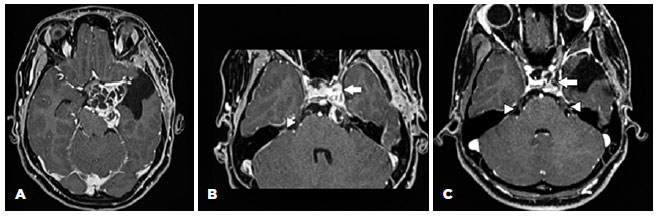

An 18-year-old female patient presented with left ptosis and exotropia after resection of a cavernous sinus schwannoma 15 months previously. Figure 1 (A and B) shows the lesion when she was referred to our service, after a prior surgery in another hospital. Figure 1C shows the postoperative aspect. Her past ocular history was unremarkable. Cranial nerve assessment revealed hypoesthesia in the left hemiface without facial weakness.